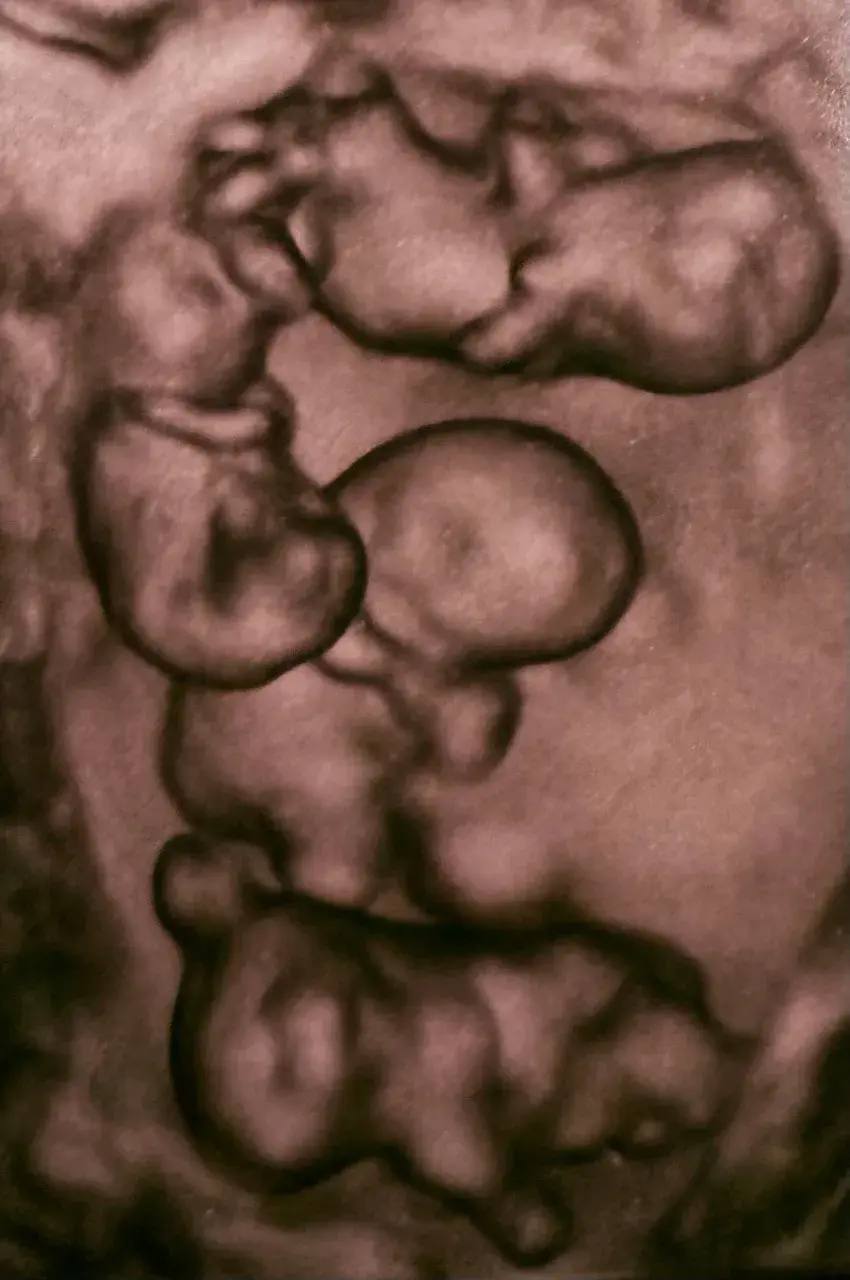

#Фотофакт : Россиянка родила четырех однояйцевых девочек-близняшек

В одном из роддомов Петербурга женщина по имени Мария родила четырёх девочек, и все они — однояйцевые близнецы. Ранее подобные случаи в России не фиксировали.

По расчётам, монохориальная, то есть однояйцевая, четверня встречается один раз на 15,5 миллиона родов. Детей удалось доносить до 32 недель. Для четверни это очень хороший срок. Вес новорождённых составил от 1360 до 1640 граммов, рост — от 37 до 41 сантиметра.